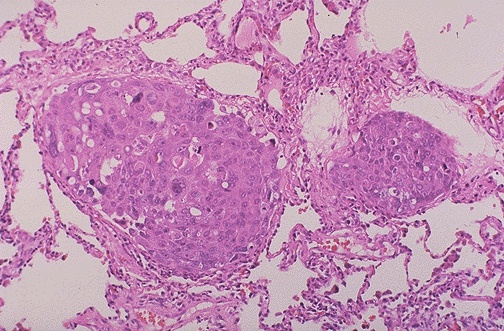

Image 5.3

The high power microscopic appearance is shown here.